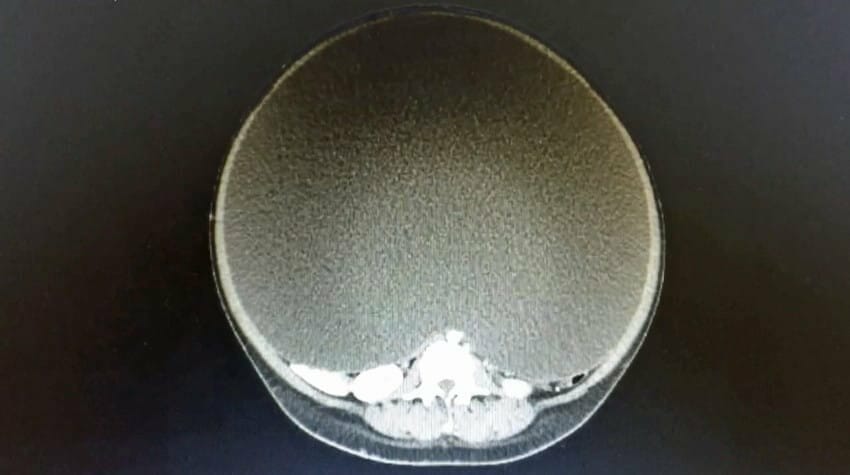

Los escaneos mostraron un quiste ovárico gigante en el vientre de la mujer. El quiste, que más tarde se encontró que pesaba unos increíbles 33 kg, había comenzado a comprimir gravemente dos de sus principales vasos sanguíneos.

“Era tan grande que ocupaba el 95 por ciento del abdomen de la paciente”, dijo el Dr. Viana en una entrevista.

El quiste ponía en peligro la vida de la mujer y había muchas posibilidades de que sufriera un ataque al corazón en cualquier momento. Es por eso que se realizó cirugía de inmediato.